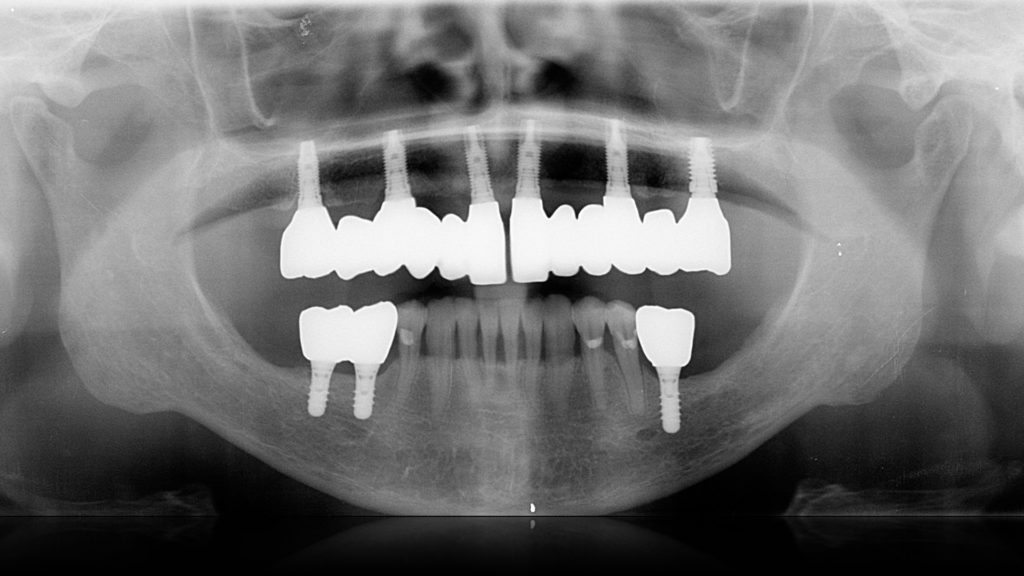

Protesi fissa: caso 5